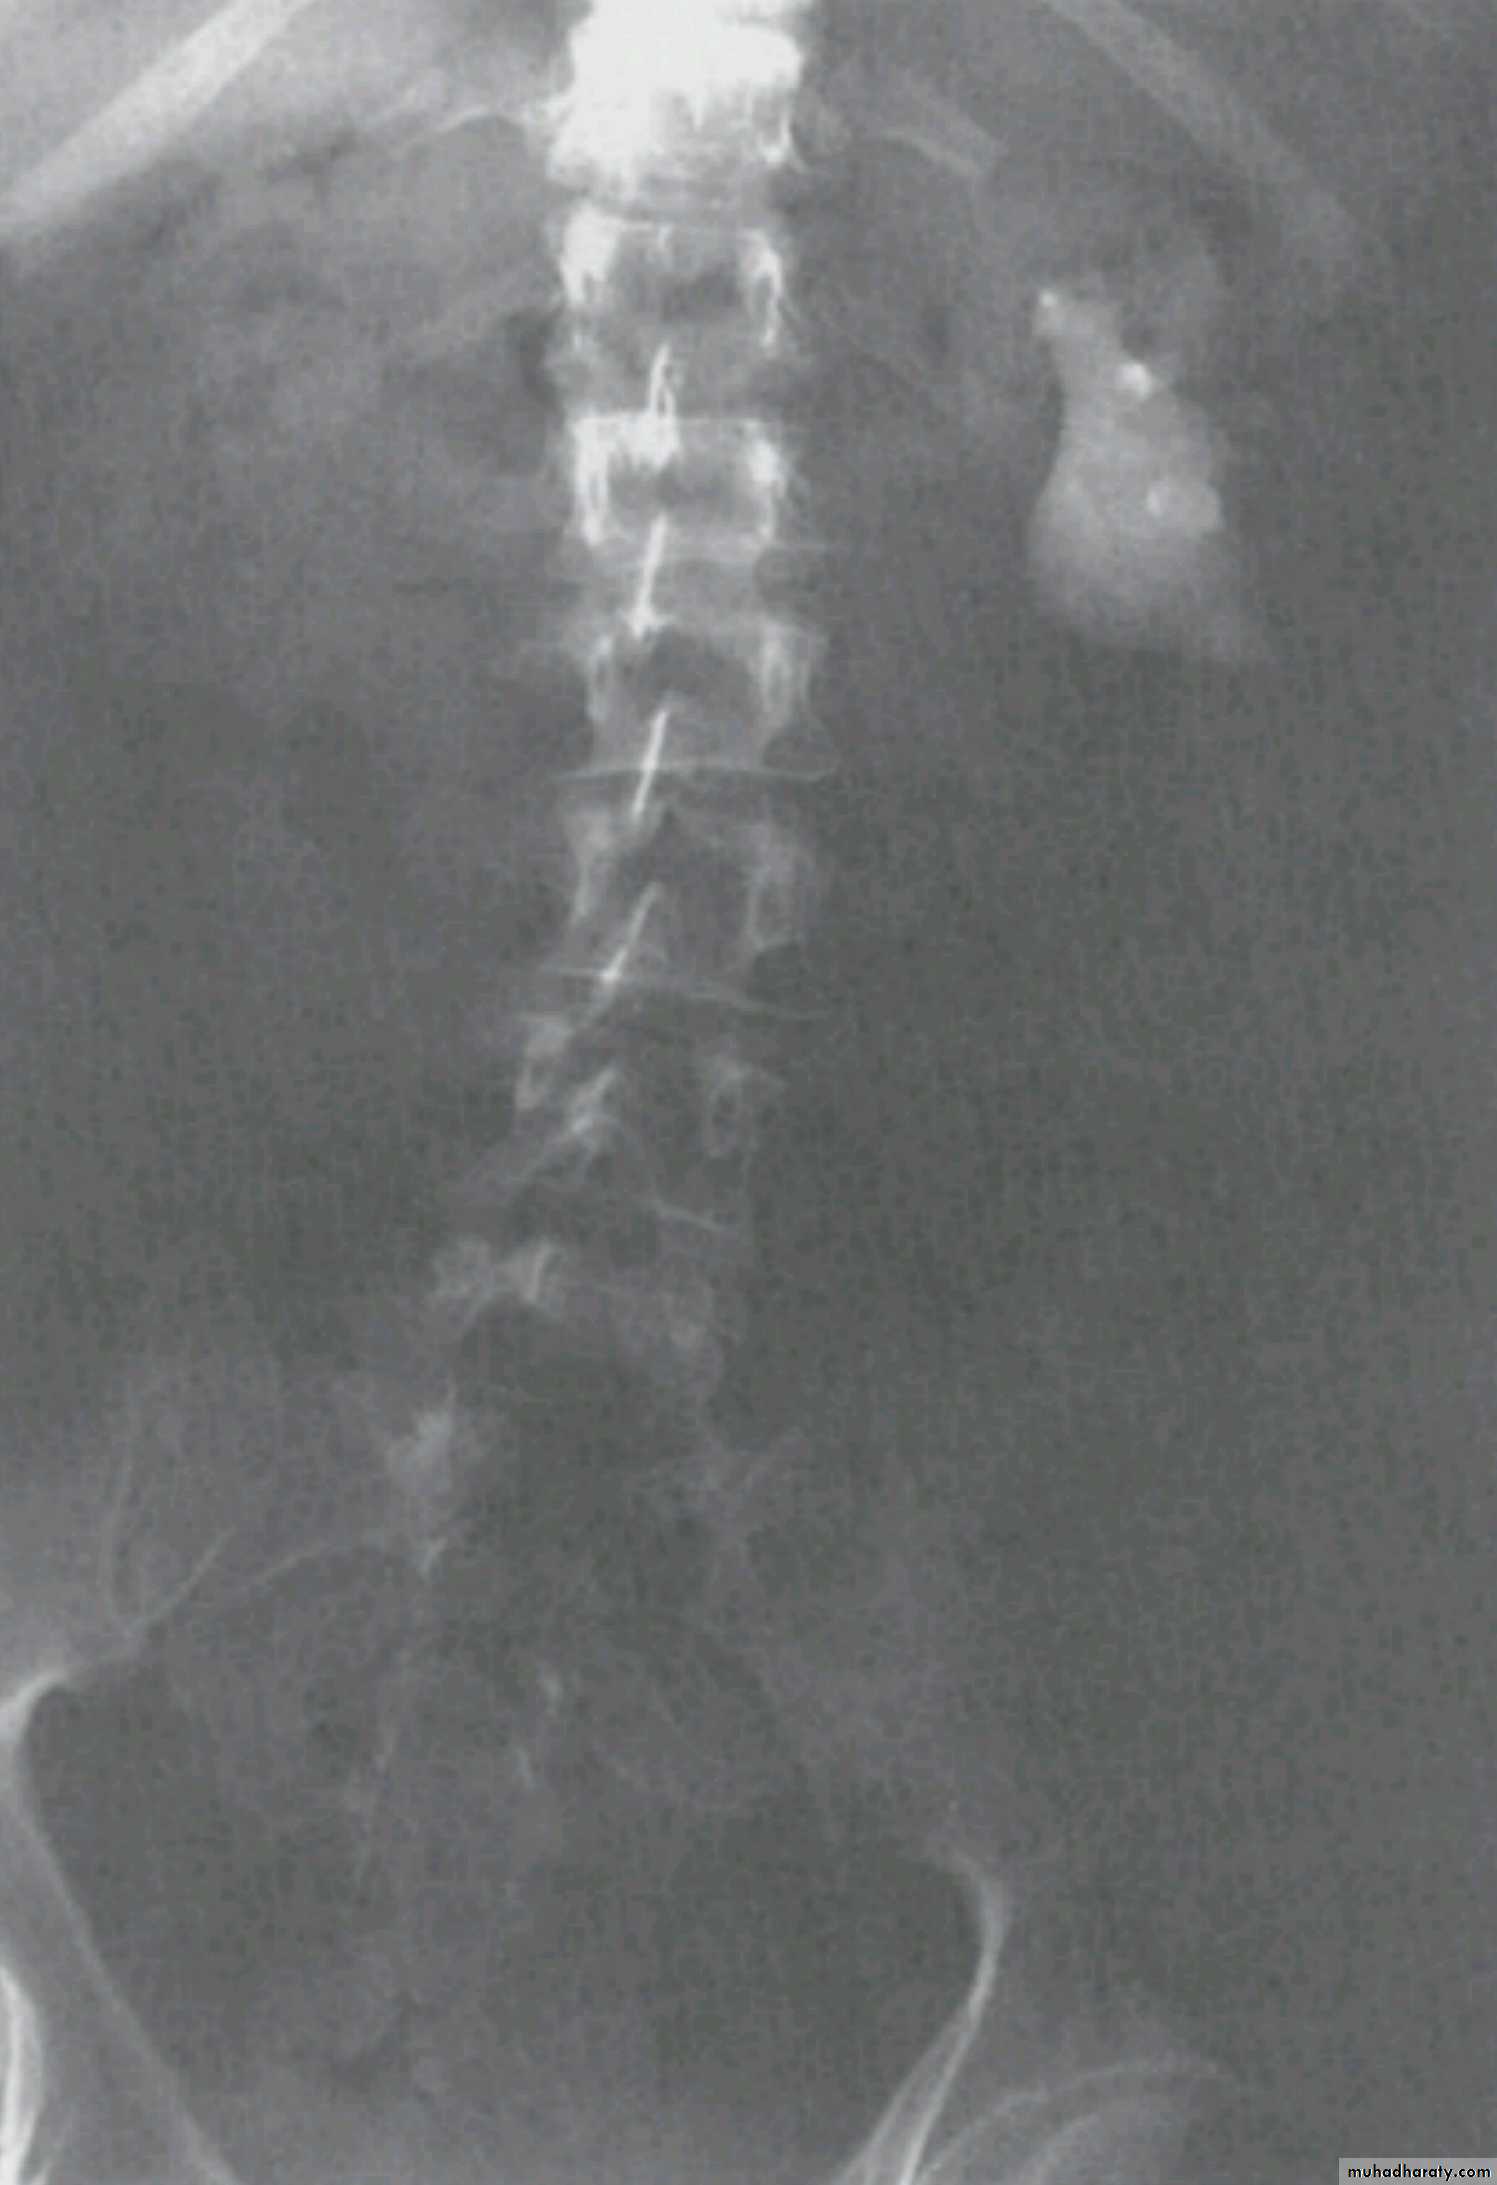

WHAT IS THE MOST APPROPRIATE RADIOLOGICAL MODALITY ?

CT scanWHAT IS THE DIAGNOSIS & THE CAUSATIVE ORGANISM ?

Struvite stone ( MAP stone ).Urea splitting microorganisms.

HOW WOULD YOU TREAT HER ?PCNL